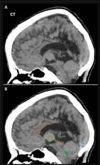

46 anos, pós trauma

Lesão axonal difusa A TC mostra discreta HSA RM T2 \* mostra focos de hemossiderina na transição substância branca e cinzenta, consistentes com LAD. Observe que a localização das microbleeds é diferente dos sangramentos CAA localizados na periferia.